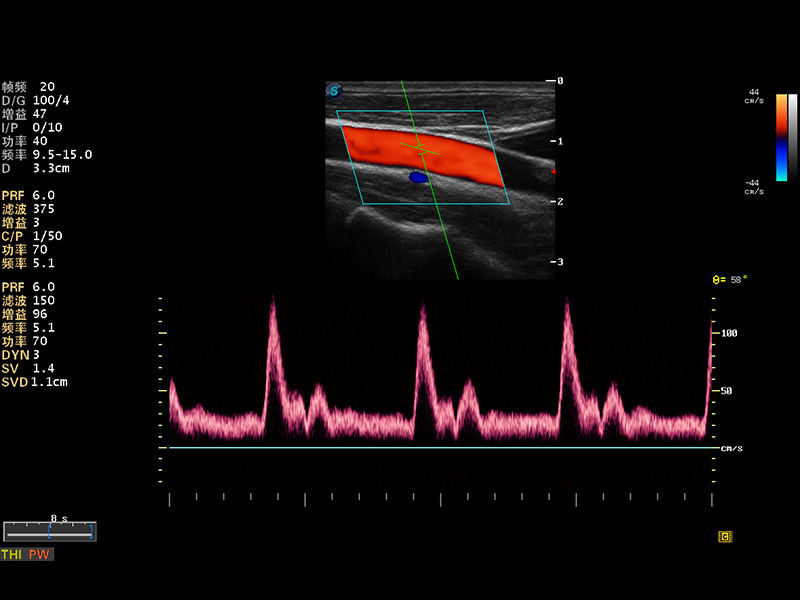

S8 EXP便携式彩色多普勒超声诊断仪是db真人体育官网研发的高端全身应用型便携彩超。高通道的VIS平台融合可视化(Visual)、智能化(Intelligent)和人性化(Smart)的特点,配以db真人体育官网自主研发生产的探头大家族,使您能够快速、准确的获得病人信息,提高工作效率的同时减轻疲劳。

多波束形成器